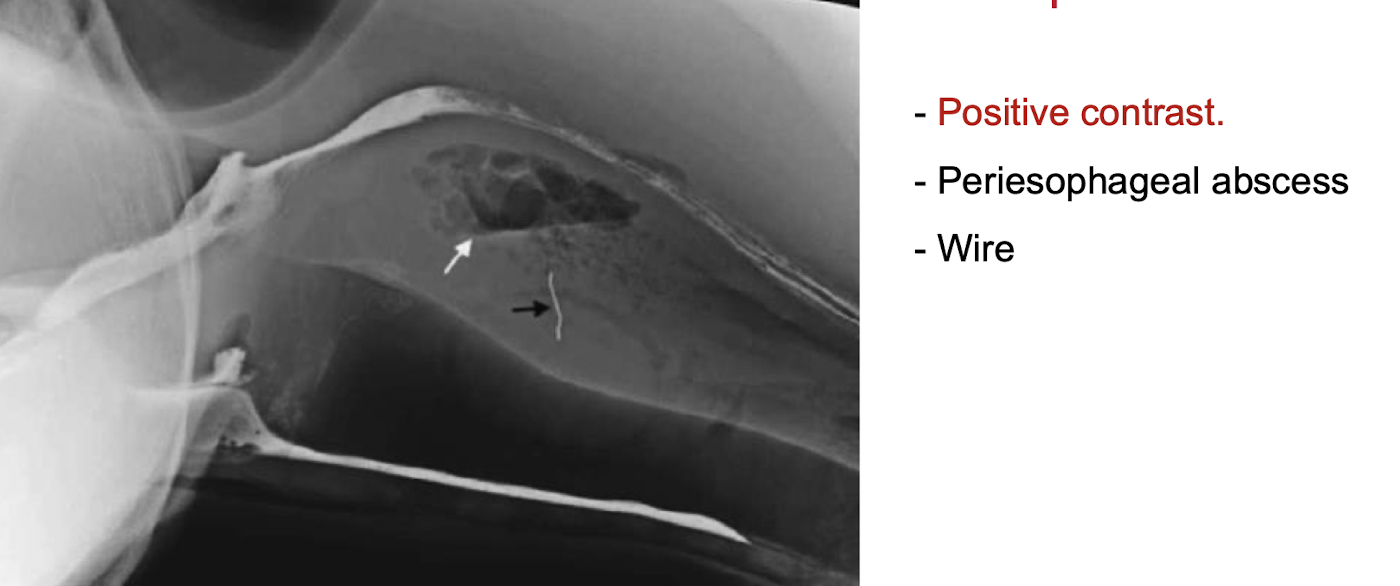

What is the purpose of performing a positive contrast esophagram?

To evaluate for esophageal obstructions, strictures, and other lesions.

periesophageal abscess